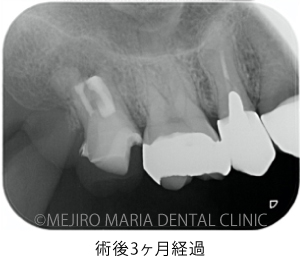

上記のエックス線写真で、術直後に根尖付近に見られた透過像(黒く見える部分)は、3ヶ月後には小さくなり、治癒傾向にあることが確認できます。また、術前に見られた歯周ポケットの改善と瘻孔(フィステル)の消失も確認できます。

歯質が少ない状態ではありますが、術後3ヶ月経過した時点で違和感の消失、病的な歯周ポケットの改善、瘻孔(フィステル)の消失が確認でき、経過は良好です。最終補綴(被せもの)へ移行後も、最低2年間は年1回ほどの経過観察を予定しています。